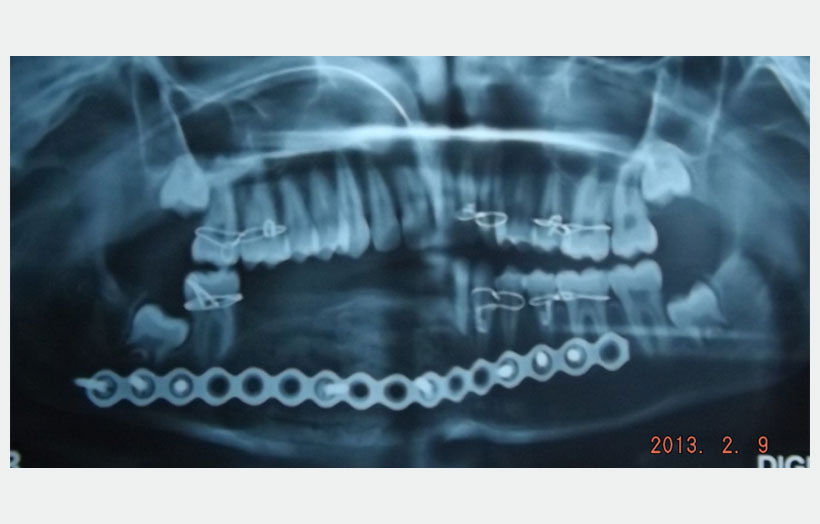

18 year old male patient came with chief complain of Swelling over Rt side of lower jaw. He was diagnosed as Benign Ossifying fibroma. Surgery was made in Feb 2013 for excision of lesion and reconstruction using Iliac crest cortico-cancellous bone graft from right side. Bone graft fixed to the defect using a reconstruction plate. After 1 year we can see adequate bone formation at the defect side. He is planed for replacement of missing teeth using 3 Alpha Dent 5×13 mm classic implants.